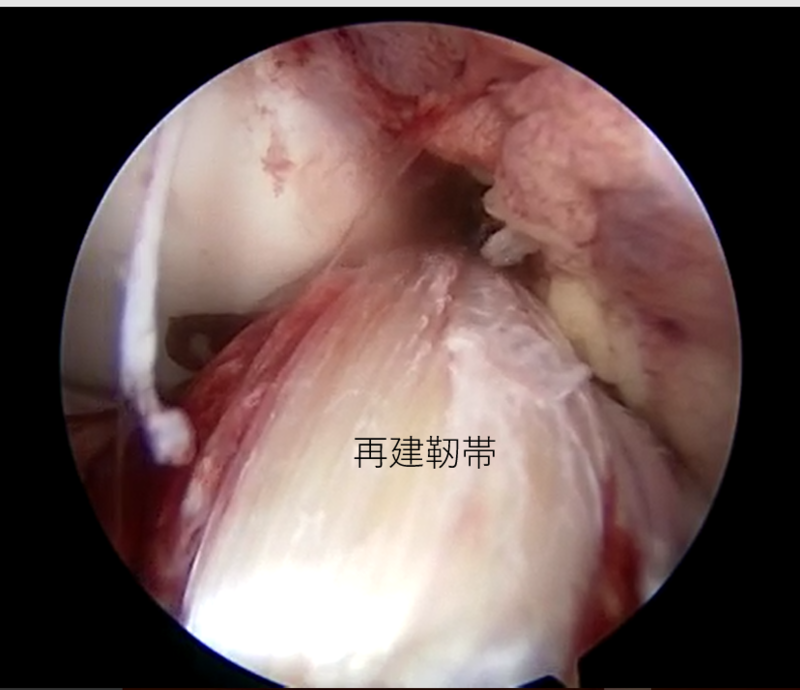

| 外側半月板問題なし | 内側半月板問題なし | 再建靭帯 |